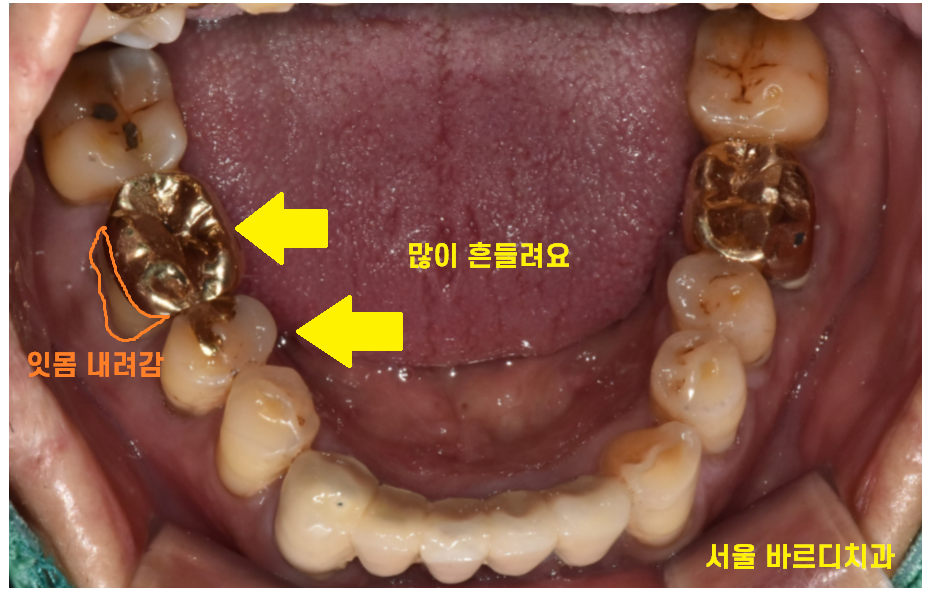

오른쪽 아래 치아가 우리해요

양치하면 괜찮은데

밥먹고 나면 아파요

오른쪽 아래 치아가 우리~하다고 내원하신 분입니다.

욱씬거리다의 사투리인데요.

쑤시는 느낌을 받으시나봅니다.

그동안은 진통제를 먹으면서

버티셨다고 해요.

밥 먹을 때는 특히 아프지만

양치하고 나면 괜찮아서

그럭저럭 버티셨다고 하셨는데요.

하남시청치과에 방문해주셨을 때

잇몸 뼈가 많이 내려가신 상황이었습니다.